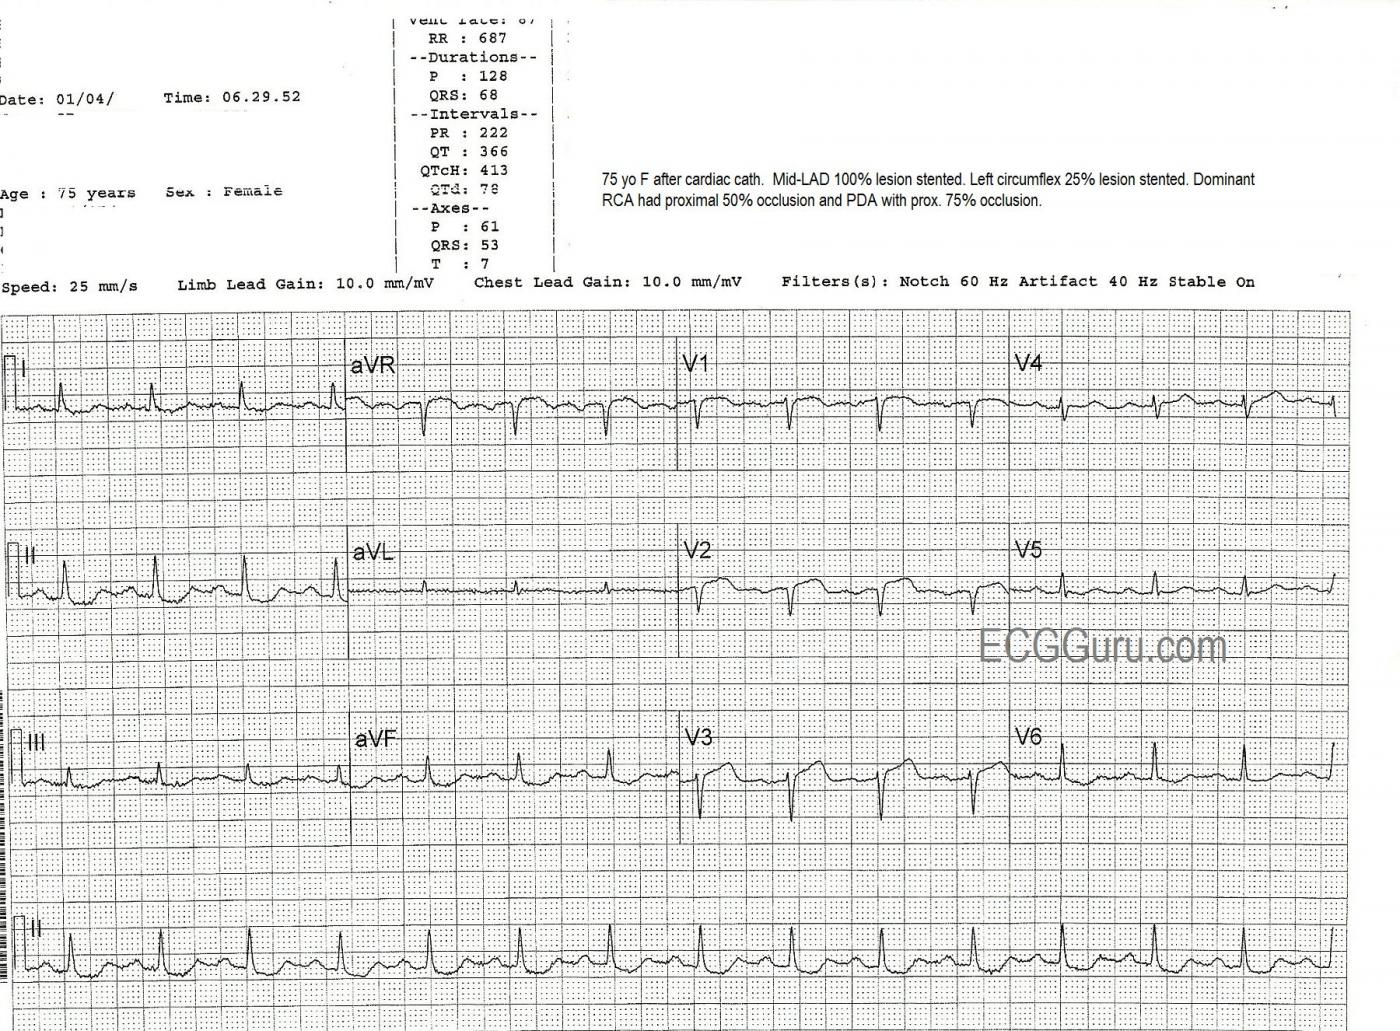

The patient was taken to the cath lab, where it was found that she had a 100% mid-left anterior descending artery occlusion, which was opened and stented. She also was found to have widespread coronary artery disease, with the left circumflex artery 25% occluded (stented), the right coronary artery (which was dominant) proximately occluded 50% and stented, and the posterior descending artery 75% occluded (stented).

The second ECG, taken at 6:29 the same morning, after the cath procedure, shows some ST elevation with coving remaining in V1 through V3, and also aVR, but now with the loss of R waves in V1 and V2 and loss of R wave voltage in V3. This represents the formation of pathological Q waves, and can be a permanent change in many cases.